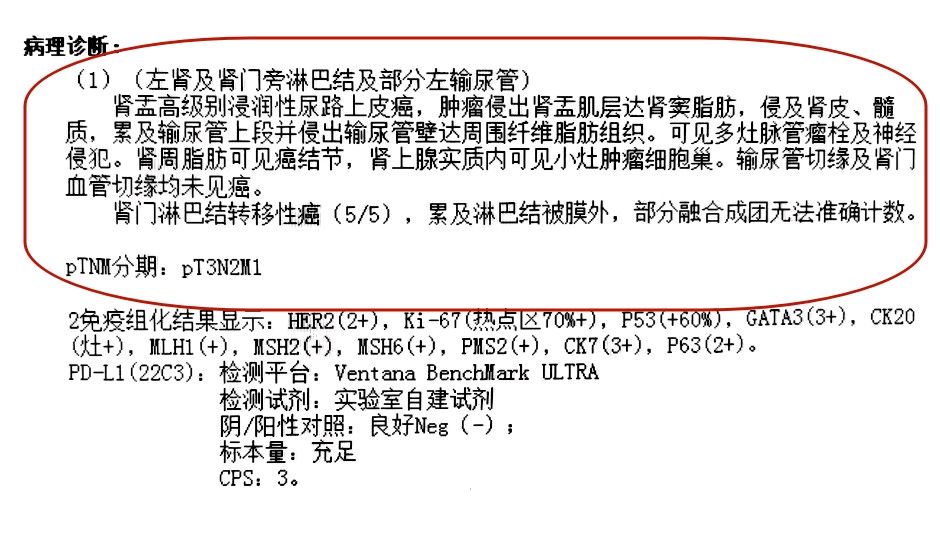

术后病理: